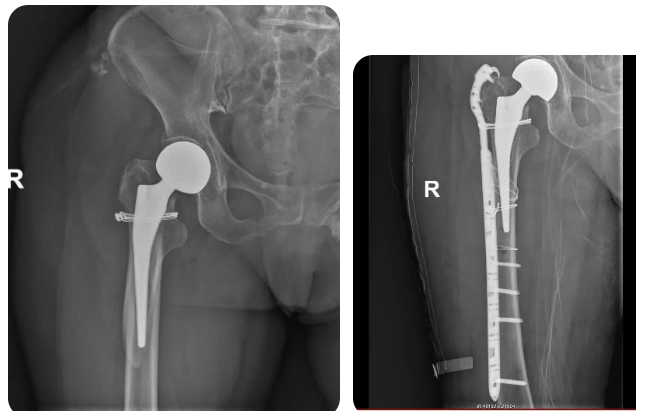

然而,命運多舛,該患者出院后沒過多久,在家中不小心再次跌倒,家屬連忙找到徐紅立副主任,來院拍片診斷為股骨假體周圍骨折,骨折的位置非常特殊——就發(fā)生在剛置換的右側人工股骨頭假體周圍,屬于臨床上處理難度較大的“假體周圍骨折”。

為盡快減輕患者痛苦,徐紅立副主任緊急組織科室進行了多學科會診,制定了周密的"右股骨假體周圍骨折切開復位內(nèi)固定術"方案。手術中,他精細操作,在保護原有右股骨假體和周圍組織的前提下,精準解剖復位固定骨折,手術順利,患者目前在進一步康復中。

徐紅立副主任介紹,假體周圍骨折是人工關節(jié)置換術后可能面臨的嚴重并發(fā)癥之一,處理起來尤為棘手。其難點在于,骨折線往往緊鄰甚至累及到固定假體,這使得常規(guī)的骨折固定方法難以有效實施。同時,接受關節(jié)置換的患者,尤其是老年群體,常常伴有不同程度的骨質(zhì)疏松,骨骼質(zhì)量欠佳,為骨折的穩(wěn)固固定增加了難度。